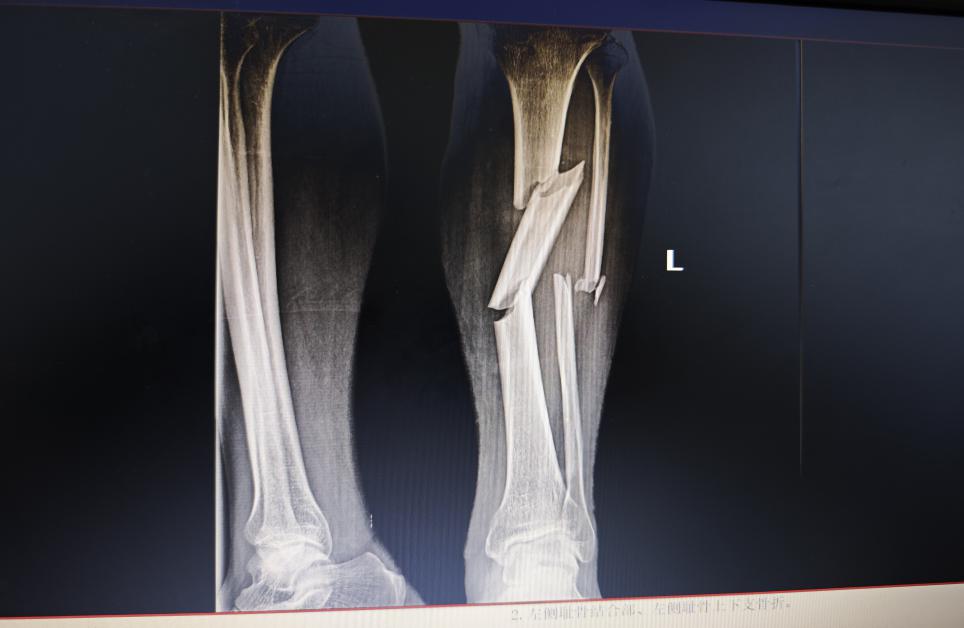

惊险一刻:小腿胫骨竟成“三节棍”

深夜的急诊科,警笛声由远及近。65岁的李叔(化名)因车祸重伤被紧急送至玉林市红十字会医院骨科二区。检查后的结果令人震惊:他的左下肢严重受伤,左侧胫骨和腓骨双双骨折,更为棘手的是,胫骨主干部位出现了两处完全性骨折,断裂的骨骼错位明显,在影像学上呈现出类似“三节棍”的惊心形态,同时伴有多处皮肤软组织挫伤。面对如此复杂的骨与软组织创伤,一场“保膝之战”悄然打响。

术前影像: